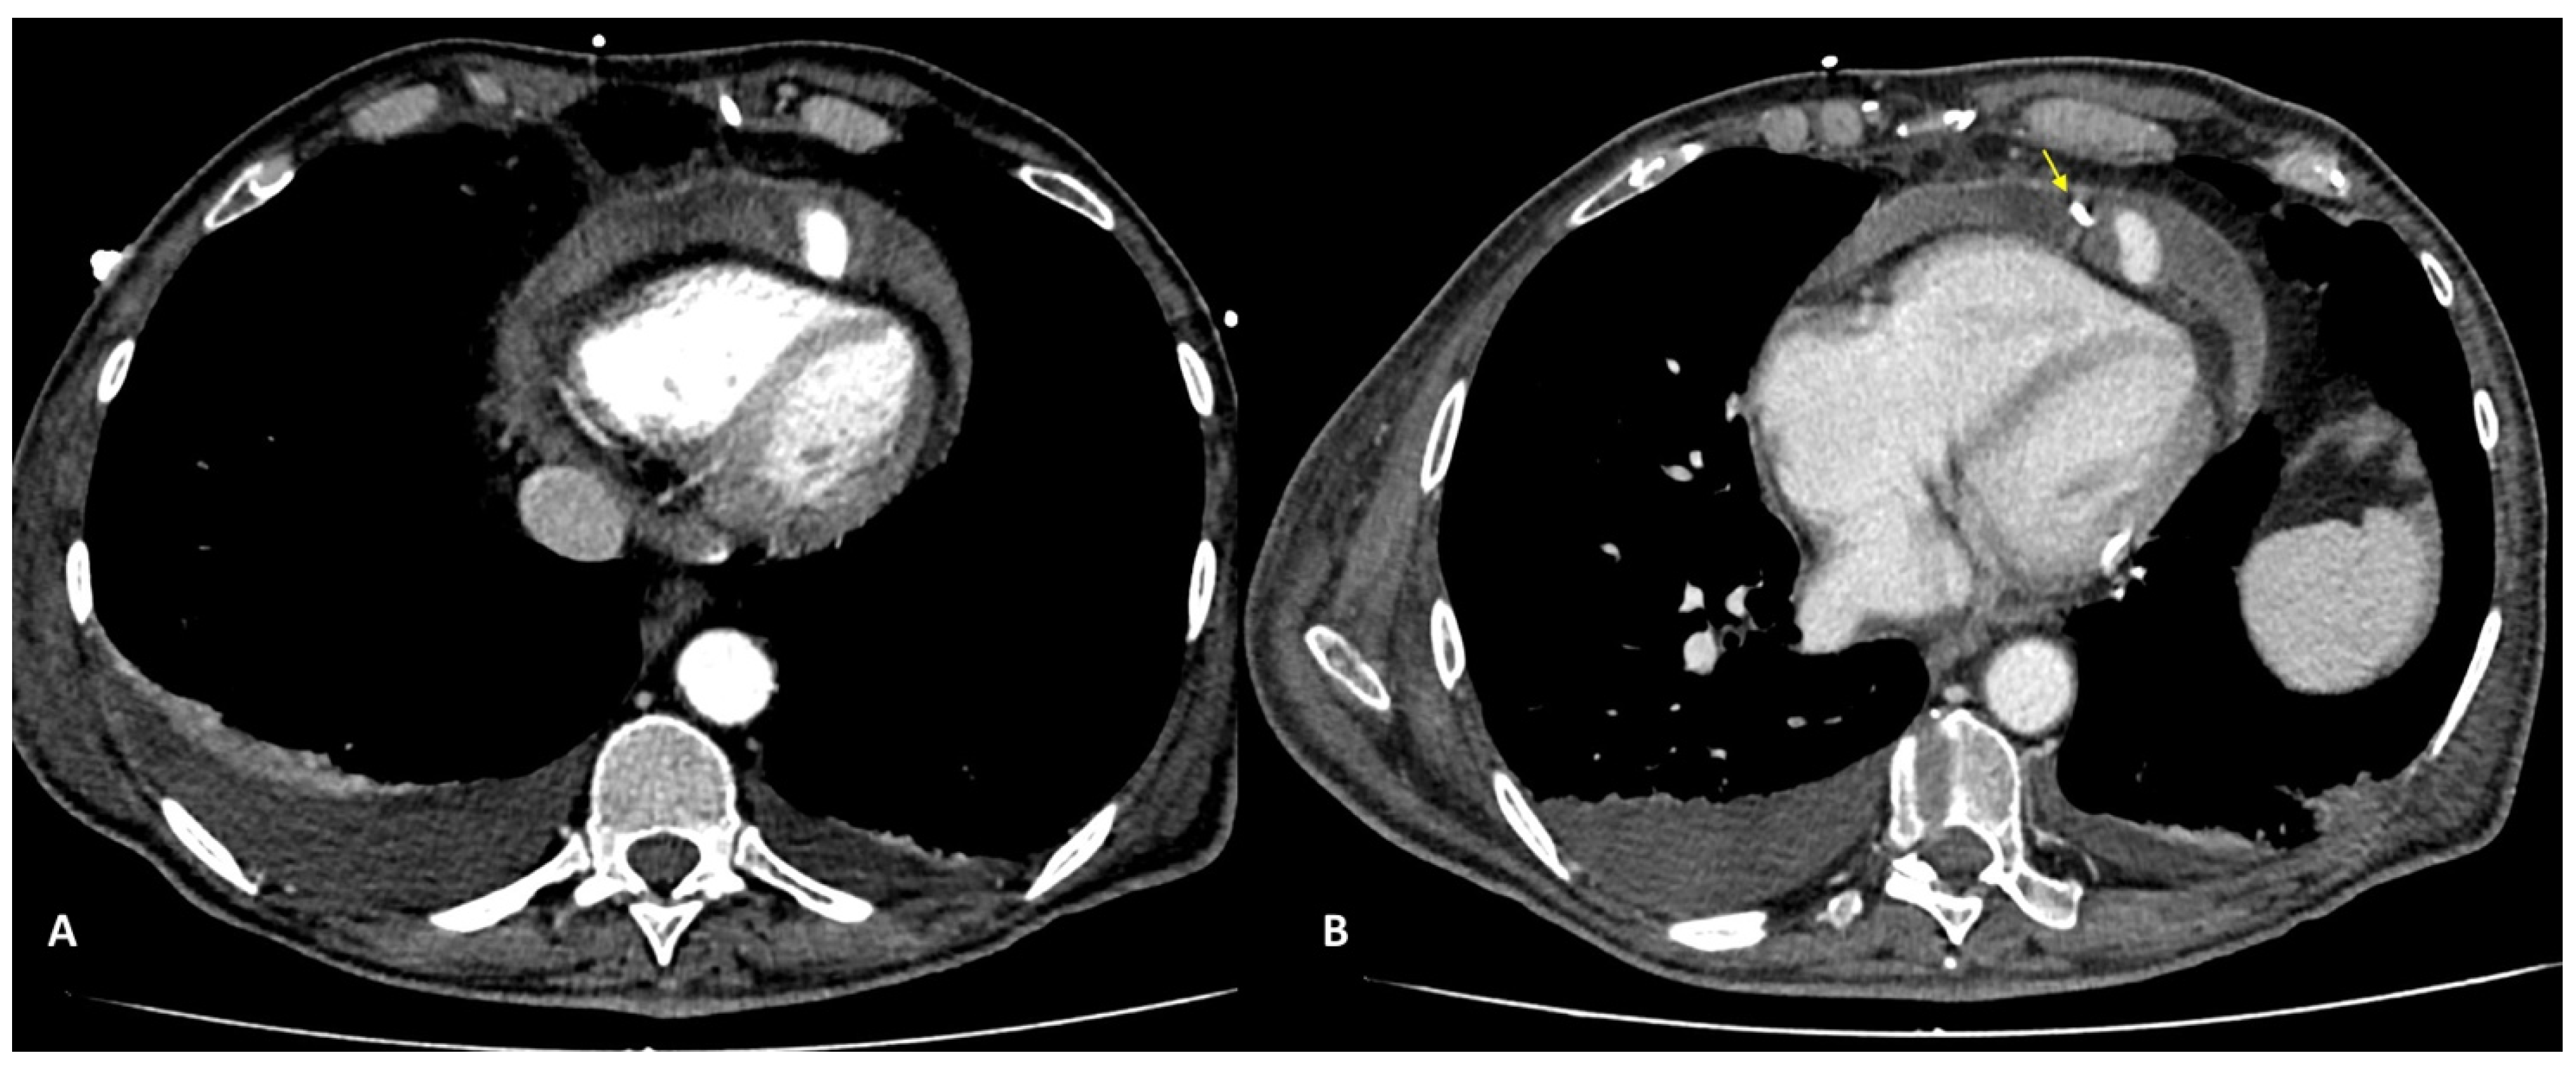

Complications less frequently presented after PTCA were vascular-wall pseudoaneurysm formation (3/27 patients, 11.1%) (Figure 2) or coronary stent migration or displacement (4/27 patients, 14.8%), which were always diagnosed in non-symptomatic patients (Figure 3 and Figure 4).

Coronary pseudoaneurysms are relatively rare and can be caused by iatrogenic procedural trauma after PTCA or, more rarely, after coronary angiography. An aneurysm is defined as >1.5 times the normal arterial diameter, but pseudoaneurysms do not involve all layers of the vessel wall. Coronary pseudoaneurysms are mostly detected incidentally and are asymptomatic, but they can result in fistulae, rupture, bleeding, tamponade, and myocardial infarction; for these reasons, a prompt diagnosis is crucial [21], and CCTA allows for a correct definition of the size, morphology and location of the lesion.

We found coronary pseudoaneurysm in two patients (7.4%), both in the left coronary artery: one in the left main coronary artery (LMCA) and one in the left anterior descending (LAD), respectively.

Figure 2. CCTA performed as follow-up acquisition after a coronary PTCA in an asymptomatic patient: axial (A) and coronal (B) multiplanar reconstructions showing distal left-main pseudoaneurysm (arrow) dimensions; 2.2 × 1.2 cm. Volume-rendering (C) image confirms the vascular sac at the edge of left main trunk.